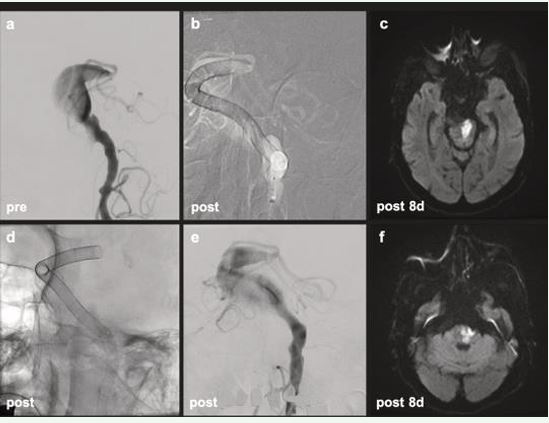

Patient 2

An 88-year-old man with a fusiform BA aneurysm underwent MRI showing a 3.5 cm lesion with mass effect. He received ticagrelor, aspirin, and dabigatran. Antiplatelet measurement confirmed adequate dual platelet receptor inhibition. The patient underwent implantation of ten overlapping FDs. Initially stable, he experienced hypotension post-procedure but recovered without focal deficits. ClotChek™ confirmed that the patient was therapeutically anticoagulated with dabigatran (382s). On postoperative day 5, the patient developed right hemiparesis, dysphagia, and dysarthria. MRI showed pontine ischemia likely due to perforator branch coverage. Dabigatran was discontinued due to nasogastric tube use and replaced with LMWH. Despite progression of local ischemia, no new infarcts were seen and flow diverter was patent. The patient was discharged to rehabilitation (Figure 2).

Figure 2 PT 2 Diagnostic (a): fusiform BA aneurysm. Road map (b), fluoroscopy (d) and post-treatment (e): perfectly adapted FDs from distal left V4 segment to mid BA, telescoping technique, covering entire fusiform segment. MRI after 8 days following treatment demonstrated pontine ischemic infarct (c, f).

Non-saccular fusiform basilar artery aneurysms represent a particularly high-risk neurovascular pathology with limited therapeutic options and poor natural history [10,11]. Endovascular reconstruction using overlapping flow diverters (FDs) has emerged as a technically feasible strategy, yet carries substantial procedural risk, including thromboembolic and ischemic complications [12,13]. Antiplatelet and anticoagulant therapy is central to reducing this risk, with recent data supporting triple therapy regimens involving two antiplatelet agents and one DOAC. Despite standardized DOAC dosing, clinical outcomes remain heterogeneous. This variability could reflect a clinically relevant spectrum of anticoagulant response among patients. Real-world evidence shows that approximately 20% of patients treated with DOACs for atrial fibrillation experience breakthrough ischemic strokes, raising concern for suboptimal pharmacodynamic effect [8]. Such patients may not achieve sufficient thrombin or factor Xa inhibition despite appropriate plasma levels. Pharmacodynamic failure may be especially consequential in the neurointerventional setting, where clot formation on stent constructs or within aneurysm sacs can result in brainstem infarction or death. The cases presented here exemplify both ends of the DOAC response spectrum. ClotChek™ testing in Patient 1 demonstrated insufficient dabigatran effect, which likely contributed to the development of catastrophic FD thrombosis. This case highlights the inadequacy of relying solely on standard dosing protocols and the need for real-time, point-of-care coagulation testing. Patient 2, in contrast, exhibited a therapeutic response by ClotChek™ and maintained patency of the stent construct, with ischemia likely attributable to hemodynamic and anatomical factors rather than pharmacologic failure. These findings reinforce the concept that pharmacodynamic variability in DOAC response can have significant clinical consequences. Incorporating bedside coagulation testing into neurointerventional practice could guide therapeutic adjustments and ultimately enhance patient outcomes. Further studies are needed to validate these findings and establish standardized protocols for measuring DOAC effect in high-risk populations.